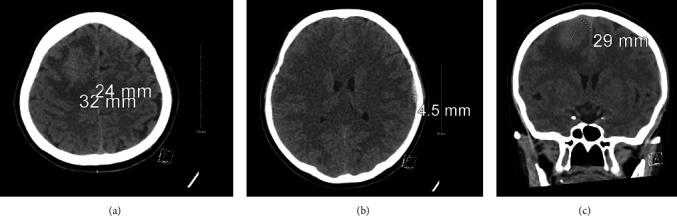

Introduction: Schistosomiasis is a parasitic infection caused by schistosome invasion of blood circulation. Neuroschistosomiasis is a severe cerebral complication that accounts for less than 2.3% of reported cases. Patients present with progressive encephalitis, seizures, or both. Management includes antiparasitic medications, steroids, and surgical intervention. Case Presentation. We report a case of a 44-year-old female who presented to the ER with a history of transient loss of consciousness (LOC) and seizure. Radiological investigations revealed a right frontal brain lesion. Histopathological results confirmed the diagnosis of schistosomiasis.